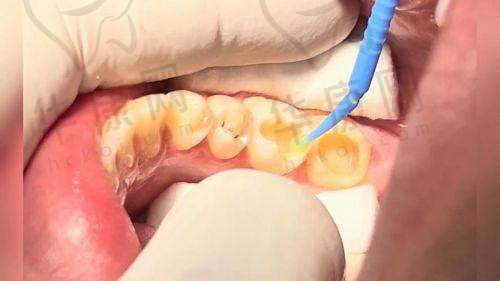

海南国雅口腔医院儿童树脂补牙之补牙过程

确定好材料后,医生就开始给孩子补牙了。首先,医生给孩子的牙齿进行了清洁和消毒,这个过程孩子没有感觉到什么不舒服。然后,医生用专精的工具把龋坏的部分一点点地磨掉,孩子说有点酸酸的感觉,但还能忍受。接着,医生把调配好的3M进口树脂材料填充到牙齿的龋洞里,一边填充一边用仪器进行固化,让树脂和牙齿更好地结合。在这个过程中,医生的动作非常轻柔、熟练,还时不时地问孩子感觉怎么样,让孩子不要害怕。整个补牙过程大概用了半个小时左右,就顺利完成了。